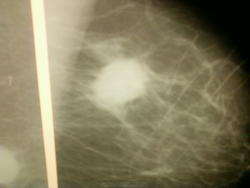

Не понятно, почему страховая компания требует M-L проекцию, по всем международным стандартам скрининг выполняется в кранио-каудальной и косой проекциях, при скрининге выполняются дополнительные проекции, видимо ваши местные "деятели" разработали свои программы обследования. Рак здесь 95%, такая же картина может быть при быстрорастущей фиброаденоме или кисте с воспалением.

во всяком случае по первому снимку я бы не смог бы написать даже подозрение на рак, только ассиметричную плотность (BIRADS 3) но дообследовал бы точно - т.е сразу бы отправил на УЗИ + конс маммолога.